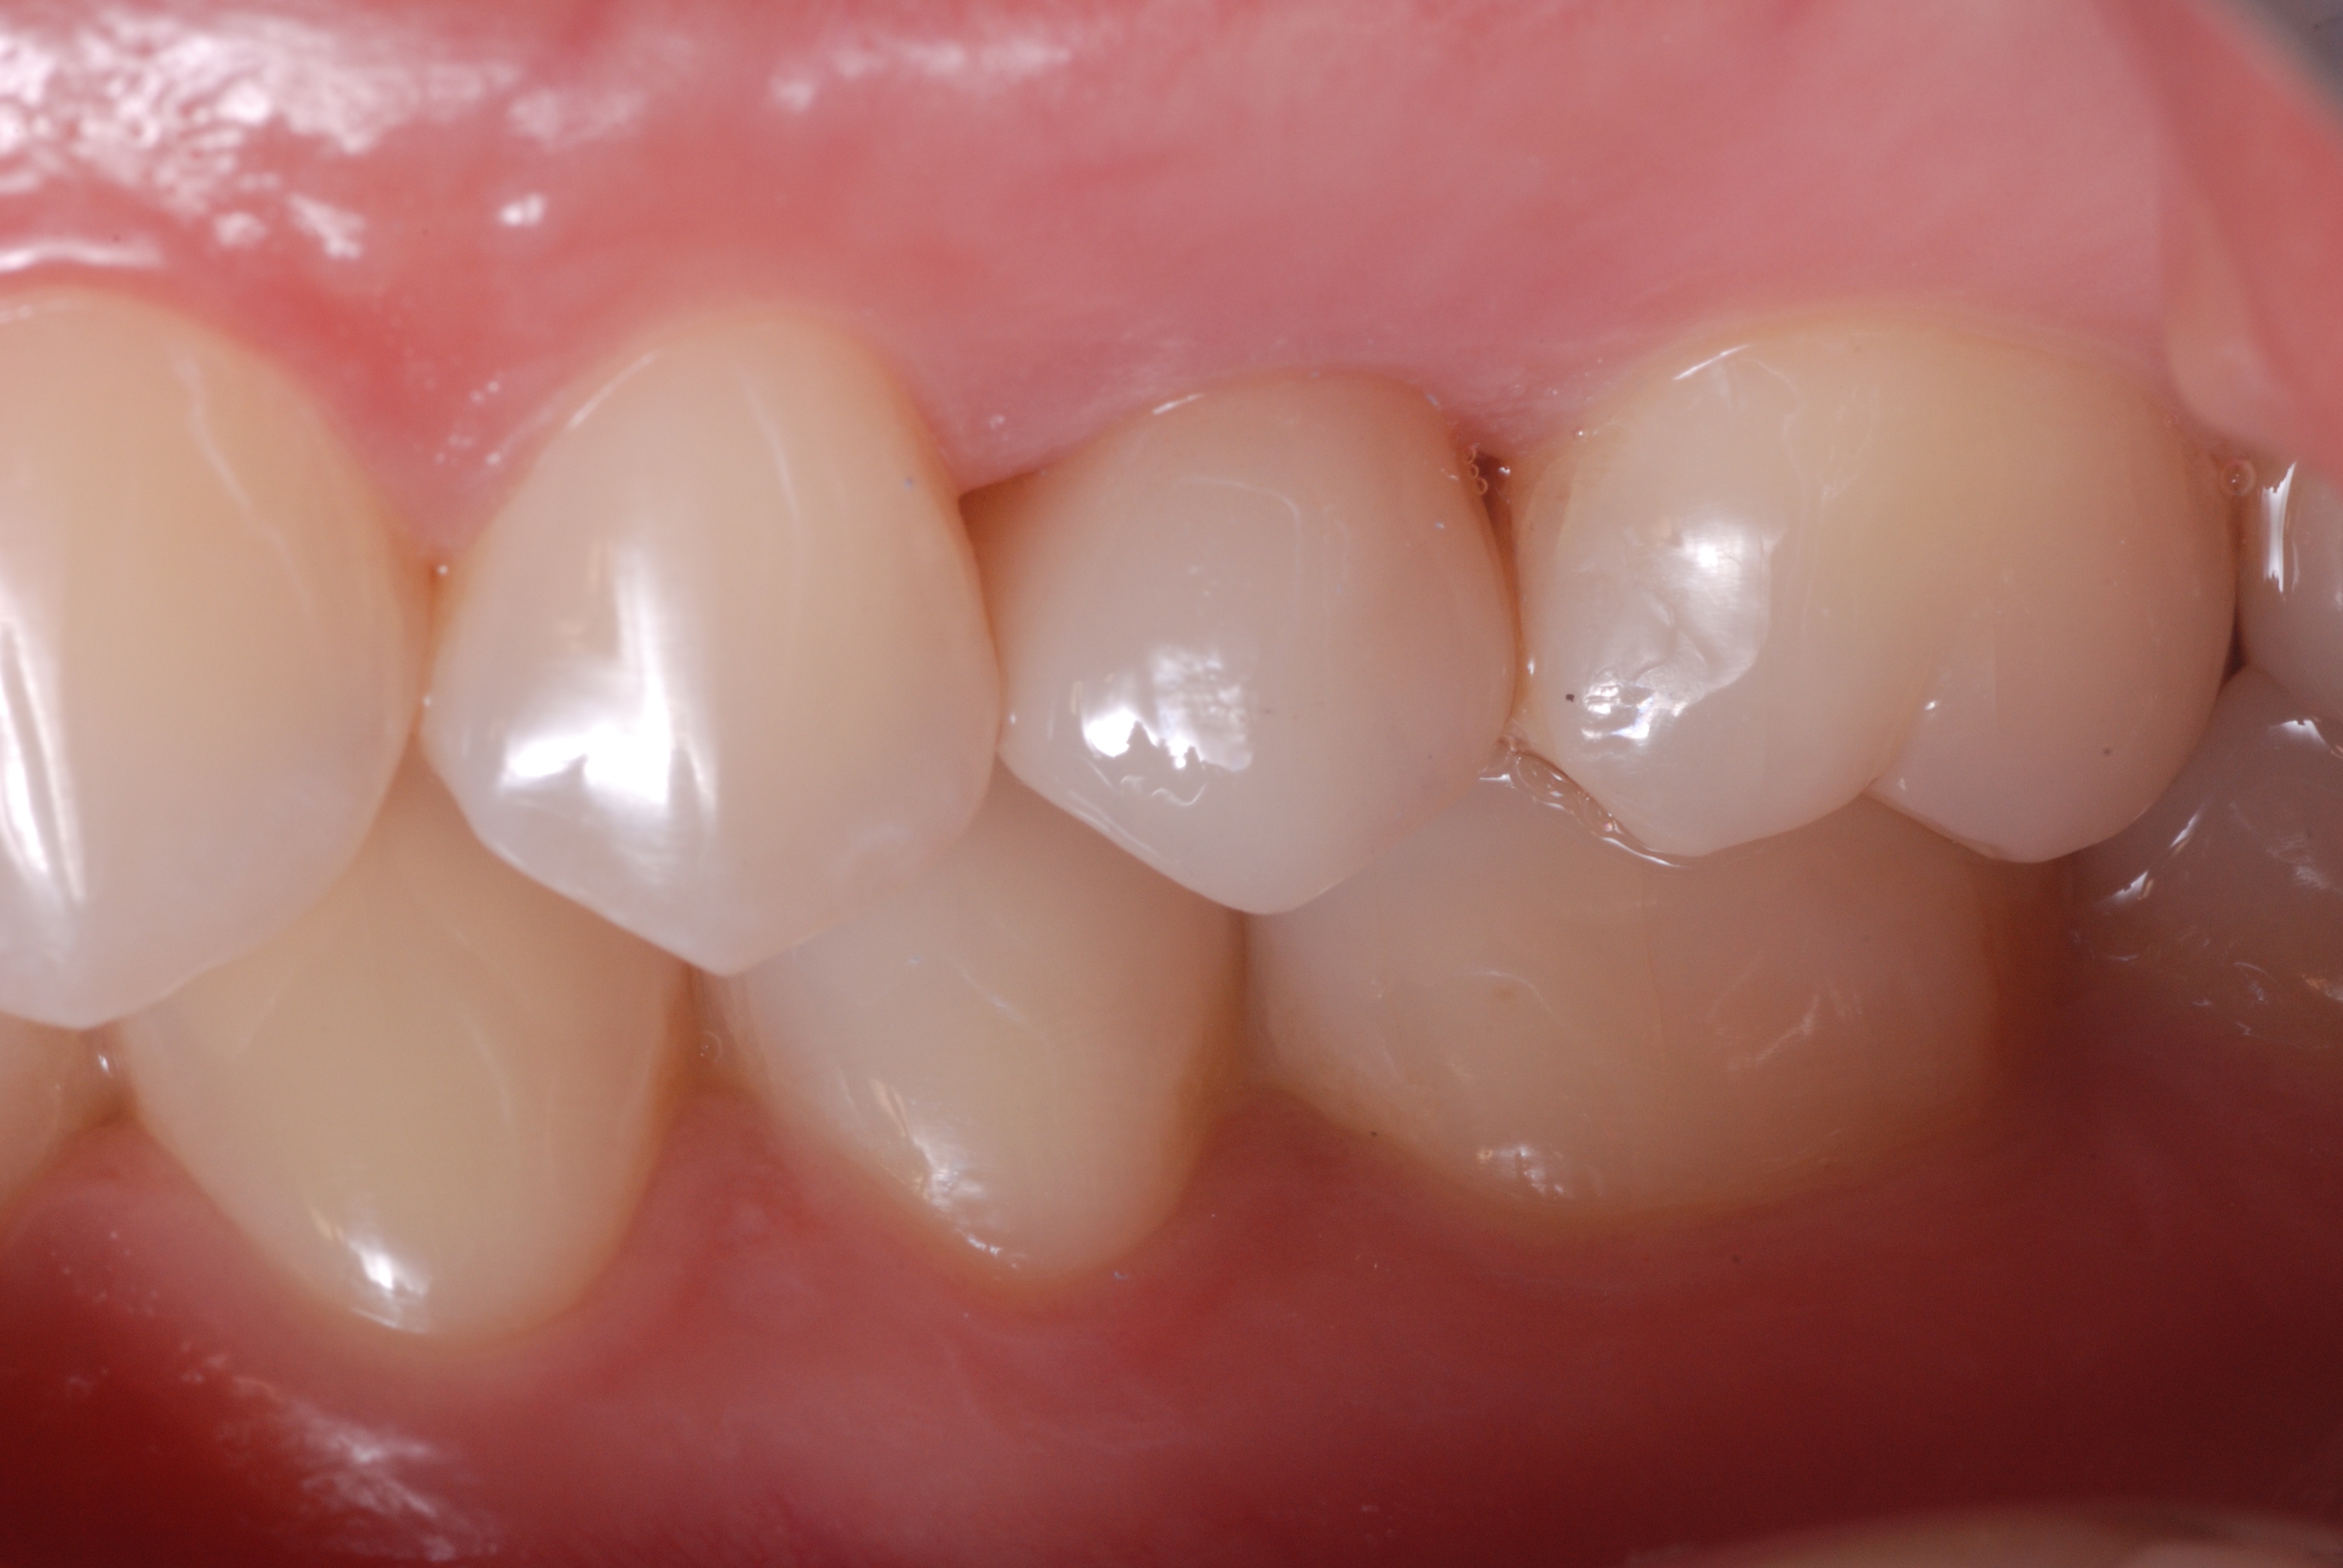

Figure 13

Figure 13. Clinical image of the same tooth at a follow-up visit.